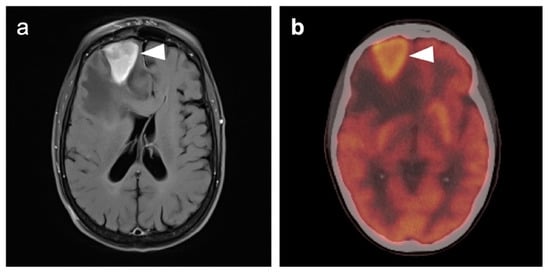

3.5. Brain Metastases

3.6. Response to Therapy